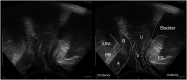

Total pelvic floor ultrasound is used for the dynamic assessment of pelvic floor dysfunction and allows multicompartmental anatomical and functional assessment. Pelvic floor dysfunction includes defaecatory, urinary and sexual dysfunction, pelvic organ prolapse and pain. It is common, increasingly recognized and associated with increasing age and multiparity. Other options for assessment include defaecation proctography and defaecation MRI. Total pelvic floor ultrasound is a cheap, safe, imaging tool, which may be performed as a first-line investigation in outpatients. It allows dynamic assessment of the entire pelvic floor, essential for treatment planning for females who often have multiple diagnoses where treatment should address all aspects of dysfunction to yield optimal results. Transvaginal scanning using a rotating single crystal probe provides sagittal views of bladder neck support anteriorly. Posterior transvaginal ultrasound may reveal rectocoele, enterocoele or intussusception whilst bearing down. The vaginal probe is also used to acquire a 360° cross-sectional image to allow anatomical visualization of the pelvic floor and provides information regarding levator plate integrity and pelvic organ alignment. Dynamic transperineal ultrasound using a conventional curved array probe provides a global view of the anterior, middle and posterior compartments and may show cystocoele, enterocoele, sigmoidocoele or rectocoele. This pictorial review provides an atlas of normal and pathological images required for global pelvic floor assessment in females presenting with defaecatory dysfunction. Total pelvic floor ultrasound may be used with complementary endoanal ultrasound to assess the sphincter complex, but this is beyond the scope of this review.